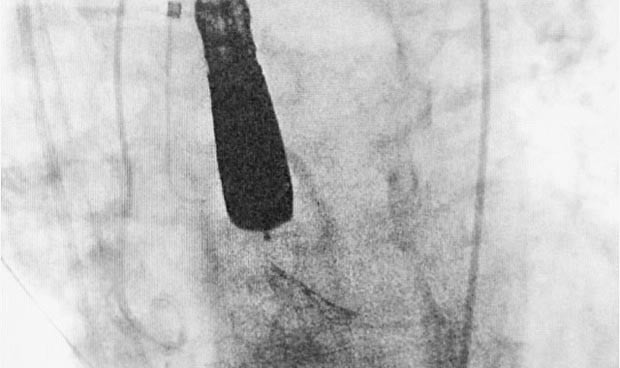

Imagen del procedimiento.

El procedimiento es manejado mediante fluoroscopia con rayos X y hace posible el implante de la válvula protésica sin parar el corazón ni someter al paciente a circulación extracorpórea, como sería necesario en una cirugía convencional.